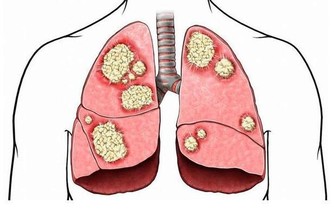

人在強烈悲哀時,會出現呼吸頻率改變、乾咳、氣短、音啞等症狀。